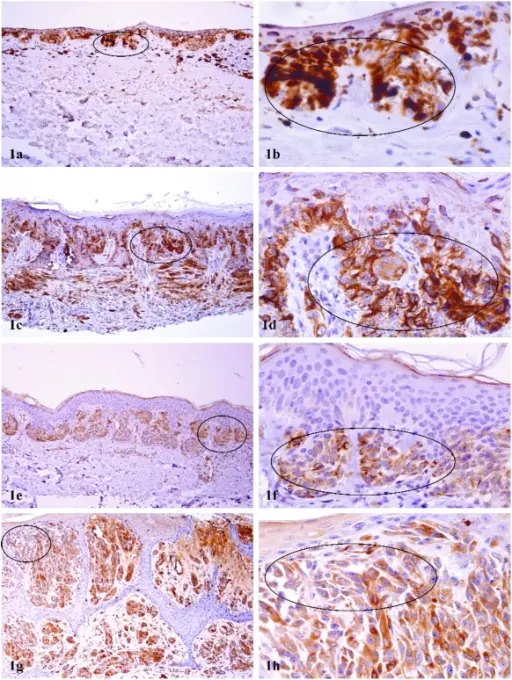

When examined under a microscope, the most common variant of renal cell carcinoma shows clear cytoplasm or a clear cell type.

Loss of the tumor suppressor gene VHL causes an increase in the growth-promoting hormone IGF-1 and the transcription factor HIF, which in turn causes an increase in the growth hormones VEGF and PDGF.

The autosomal dominant illness known as von Hippel-Lindau disease increases the risk of renal cell carcinoma (RCC) and cerebellar hemangioblastoma by inactivating the VHL gene.